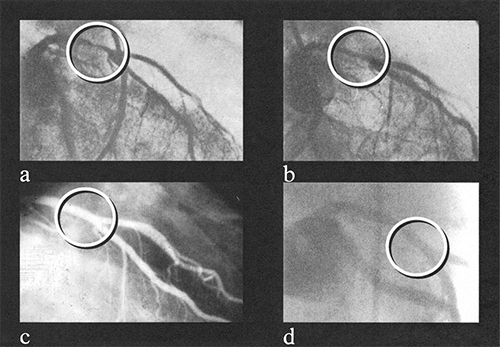

Dotter는 1964년 세계 최초로 죽상경화로 좁아진 다리의 동맥에 동축도자를 통과시켜 괴사되는 다리와 발을 구하여 경혈관 중재술의 첫 발을 내딛었다. 그러나 Forssmann과 Dotter는 찬사보다는 비웃음을 사고 버려졌다. Dotter의 방법을 계속하여 연구하고 시술한 Zeitler의 교육을 받은 Grüntzig는 1974년 Porstmann의 Latex Balloon Catheter를 변형하여 double lumen 카테타를 만들어 말초혈관을 뚫는데 쓴다. 그 후 이 카테타를 더 작게 만들었으며 개에 이어서 사람 사체에 실험하고, 다혈관질환으로 수술할 환자의 노출된 혈관에 실험하여 성공하였다. Grüntzig의 첫번째 비수술적 관상동맥 확장의 성공 (Zurich, Swiss,1977)은 좌전하행지의 근위부, 3 mm 길이, 80% 협착 병변에 대한 풍선확장술이다. 결과는 1977년 American Heart Association에서 발표되었다. 이 발표는 그때까지 혈관성형술을 연구하던 학자들의 세계에 아무런 시샘이 없는 큰 충격과 환호를 자아낸다. (환자는 성공적인 풍선확장술 이후 흉통 없이 잘 지냈고 이후 관상동맥 혈관성형술 10주년 기념으로 그가 마지막으로 봉사했던 에모리 대학에서 추적 관상동맥 조영술을 시행하였는데 10년 전에 시술하였던 좌전하행지는 다시 좁아지지 않고 거의 완전한 모습을 보였다.) 이어서 관상동맥 중재술은 독일 (Kaltenbach, Kober, Frankfurt), 미국 (Myler, San Francisco; Stertzer, New York, 1978.3.)으로 빠르게 확산되었다.

그림 1. 1977년 9월 16일 Andreas Grüntzig에 의한 세계 최초의 관상동맥 풍선확장술 및 추적 관상동맥 조영술 사진.

(a) 시술 전 근위부 좌전하행지 협착, (b) 관상동맥 풍선확장술 직후,

(C) 관상동맥 풍선확장술 10년 후, (d) 관상동맥 풍선확장술 23년 후

(Circulation. 2000;102:IV-81–IV-86.)